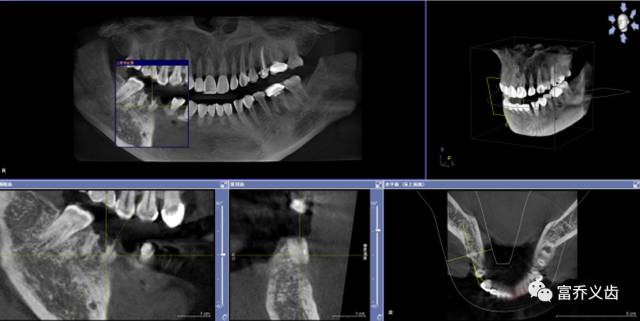

种植前曲面断层以及CBCT片